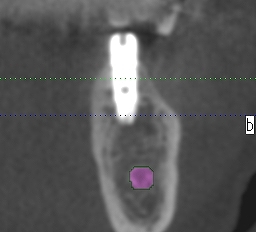

術前のCTになります

5番部になります

先が細くて中が開けてきます

4mmの13mmというインプラントを埋入